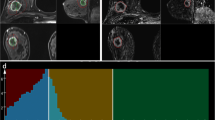

To investigate the diagnostic capability of whole-lesion (WL) histogram and texture analysis of dynamic contrast-enhanced (DCE) MRI inline-generated quantitative parametric maps using CAIPIRINHA-Dixon-TWIST-VIBE (CDTV) to differentiate malignant from benign breast lesions and breast cancer subtypes.

From February 2018 to November 2018, DCE MRI using CDTV was performed on 211 patients. The inline-generated parametric maps included Ktrans, kep, Ve, and IAUGC60. Histogram and texture features were extracted from the above parametric maps respectively based on a WL analysis. Student’s t tests, one-way ANOVAs, Mann-Whitney U tests, Jonckheere-Terpstra tests, and ROC curves were used for statistical analysis.

Compared with benign breast lesions, malignant breast lesions showed significantly higher Ktrans_median, 5th percentile, entropy, and diff-entropy, IAUGC60_median, 5th percentile, entropy, and diff-entropy, kep_mean, median, 5th percentile, entropy, and diff-entropy, and Ve_95th percentile, diff-variance, and contrast, and significantly lower kep_skewness and Ve_SD, entropy, diff-entropy, and skewness (all p ≤ 0.011). The combination of all the extracted parameters yielded an AUC of 0.85 (sensitivity 76%, specificity 86%). kep_contrast showed a significant difference among different subtypes of breast cancer (p = 0.006). kep_skewness showed a significant difference between lymph node–positive and lymph node–negative breast cancer (p = 0.007). The IAGC60_5th percentile had an AUC of 0.71 (sensitivity 50%, specificity 91%) for differentiating between high- and low-proliferation groups of breast cancer.